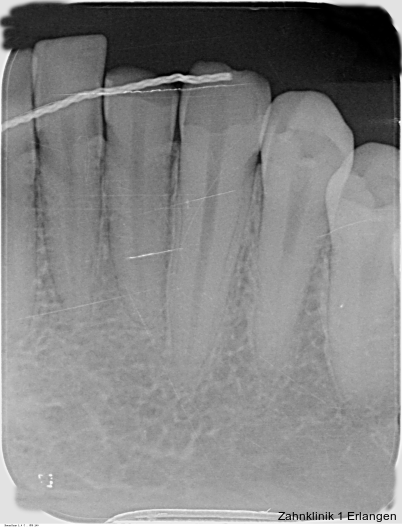

Zu den wesentlichen diagnostischen Verfahren, die zur Erfassung des Pulpastatus herangezogen werden, gehören neben der Inspektion und der röntgenologischen Bildgebung die Sensibilitätsprüfung sowie der Perkussionstest. Der Inspektion kommt insbesondere bei der Erstbehandlung eine wesentliche Rolle zu. Hierbei wird abgeklärt, ob es sich bei Zahnfrakturen um eine schmelzbegrenzte Verletzung handelt, ob das Dentin mitbetroffen und ob zusätzlich die Pulpa exponiert ist. Bei Dislokationsverletzungen wird das Ausmaß der Positionsveränderung erfasst und ob zusätzliche Gewebe wie Knochenstrukturen oder umliegende Weichgewebe betroffen sind. Auch können Farbveränderungen des Zahnes erfasst werden. Die Röntgendiagnostik zum Zeitpunkt des Unfalles gibt Aufschluss über die Größe des Pulpenkavums und das Lumen des Wurzelkanals, den Stand des Wurzelwachstums und die periapikalen Verhältnisse. Des Weiteren finden sich möglicherweise Hinweise auf eine Wurzelfraktur.

Der Perkussionstest gibt per se keinen Aufschluss über den Zustand der Pulpa. Schmerzen bei Perkussion sind Ausdruck eines geschädigten Parodonts. Im Rahmen der Nachkontrollen kann jedoch ein positiver Perkussionstest auf eine apikale Parodontitis und somit indirekt auf eine eingetretene Pulpanekrose hinweisen. Weitere wichtige Informationen kann beim Perkussionstest auch der Klopfschall liefern, der nach Dislokationsverletzungen verändert ist (heller bei intrusiver und dumpfer bei lateraler oder extrusiver Dislokation) und der im Rahmen der Nachkontrollen frühzeitig Hinweise auf eine beginnende knöcherne Ersatzresorption liefern kann.

Bei ausgeprägten Dislokationsverletzungen stellt die Schädigung des Parodonts die dominierende Verletzung dar, die auch zu Spätfolgen und Komplikationen führen kann. Verletzungen des Endodonts sind im Hinblick auf den Zahnerhalt vergleichsweise unbedeutender, da die Wurzelkanalbehandlung eine Infektion relativ sicher verhindern oder beseitigen kann. Die Erstversorgung schließt im Wesentlichen die Repositionierung und Schienung zur Ruhigstellung der betroffenen Zähne ein.3 Spätestens ab einer Positionsveränderung von 2 mm ist bei Zähnen mit abgeschlossenem Wurzelwachstum sicher von einem irreparablen Schaden der Pulpa auszugehen.2 Wichtig ist es, zeitnah, in der Regel während der Schienungsdauer, die Wurzelkanalbehandlung einzuleiten, um eine bakterielle Besiedelung des Wurzelkanals zu verhindern. Dabei reicht es zunächst aus, den Zahn zu eröffnen, desinfizierend zu spülen und eine medikamentöse Einlage einzubringen. Wird dies unterlassen, entwickeln sich bei entsprechender parodontaler Schädigung infektionsbedingte Resorptionen, die rasch fortschreiten und innerhalb relativ kurzer Zeit bis zum Zahnverlust führen können.